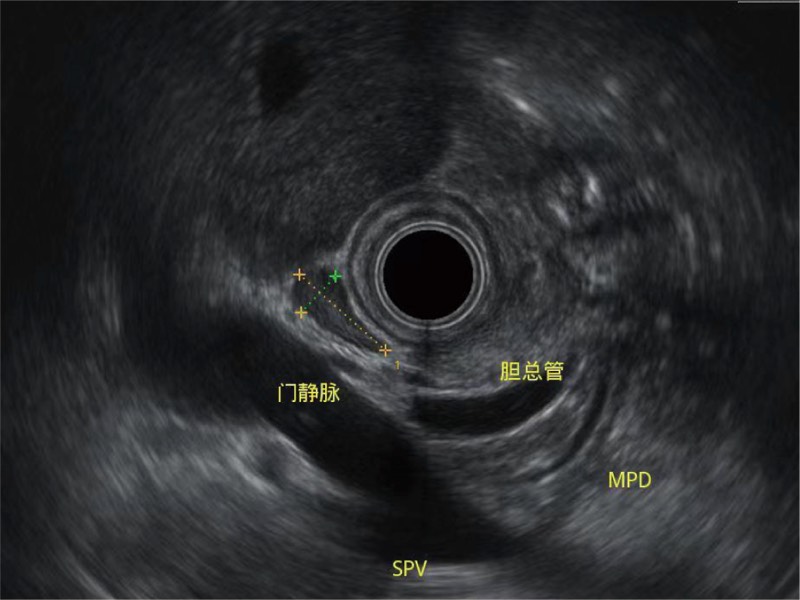

清晰显示胆总管及周围血管分布

肝左叶和肝静脉的横截面